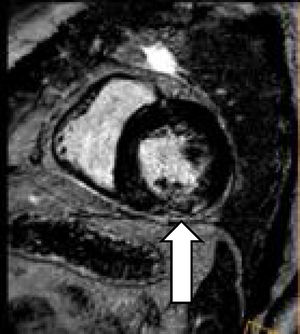

El paciente siguió tratamiento vasodilatador, y en el control clínico a los 2 meses se encontraba normotenso y asintomático. Un nuevo ecocardiograma transtorácico no mostró cambios respecto del anterior, excepto una mejoría de la función sistólica. El ecocardiograma transesofágico confirma los datos descartando foramen oval permeable. Se repite CRM que muestra: ventrículo izquierdo con hipertrofia concéntrica moderada, no dilatado, sin alteraciones de la contractilidad segmentaria y función sistólica normal (FE 70%) y persistencia del patrón parcheado intramiocárdico en el segmento medio inferolateral e inferior del ventrículo izquierdo sin necrosis, sugerente de sarcoidosis versus enfermedad de Fabry.

Hallazgos morfológicos e inmunofenotípicos compatibles con lesión fibroinflamatoria mediastínica relacionada con IgG4. La IgG4 sérica es de 130mg/dl. Las baciloscopias y cultivos para micobacterias de las muestras obtenidas fueron negativas, y se descartó por completo la presencia de proceso linfoproliferativo. Con el diagnóstico de enfermedad relacionada con IgG4 con afectación mediastínica y, probablemente, cardíaca, se inicia tratamiento inmunosupresor con prednisona (1mg/kg/día) y azatioprina (a dosis crecientes hasta 2mg/kg/día). El paciente presenta buena respuesta clínica, con reducción de las imágenes de adenopatías detectadas por TC, así como la CRM de control que, tras 4 meses de tratamiento inmunosupresor, muestra reducción del patrón intramiocárdico descrito anteriormente en el segmento medio inferolateral e inferior del ventrículo izquierdo sin necrosis (fig. 2).